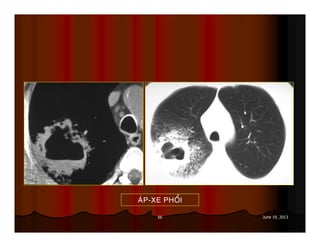

AÙP-XE PHOÅI

66 June 19,2013 AÙP-XE PHOÅI